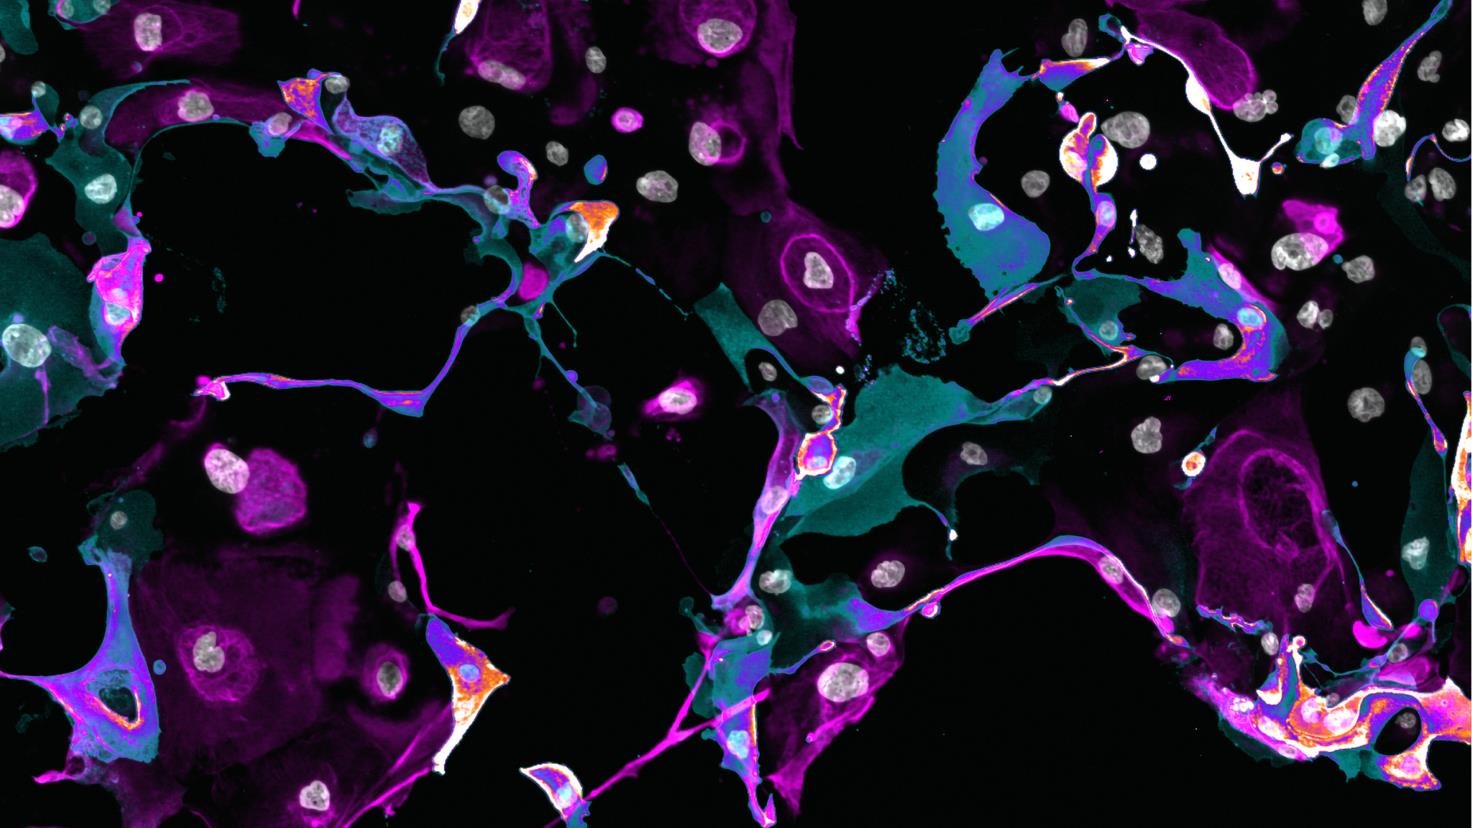

His research specialises in understanding the molecular variation in endometriosis that underlies individual differences in disease and treatment response. He established the Endometriosis Research Queensland Study (ERQS), one of Australia’s largest endometriosis studies, providing key insights into genetic and cellular signatures that can guide personalised treatment strategies and pioneering patient-derived endometrial organoids—miniature ‘avatars’ that could transform the trial-and-error approach to therapy into precise, evidence based personalised care.